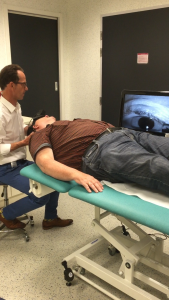

Ruim 12 uur onderweg geweest en 578 kilometers gereden (Leeuwarden-Antwerpen vv) zijn wij (mijn vrouw en ik) blij maar wel moe dat we dit bezoek aan professor dr. Floris Wuyts werkzaam aan het UZA te Antwerpen hebben volbracht. Het heeft mij in ieder geval een nieuwe diagnose opgeleverd nl. Vestibulaire Paroxysmien (VP).Na een intake gesprek met NKO arts Van Haesendonck-Gilles en professor Wuyts, heb ik mijn verzamelde medische gegevens, een gedetailleerde overzicht van de evenwichtsstoornissen vanaf 2012 tot heden en een ingevulde SO STONED formulier ter beschikking gesteld, zodat er een grote hoeveelheid gegevens aanwezig was omtrent mijn ziekteverloop. Vervolgens heb ik nog een uitgebreide gehoortest gedaan en tenslotte kreeg ik een bril op waardoor Floris mijn oog bewegingen kon zien door mij in een verschillende houdingen te plaatsen. Als er een vorm van duizeligheid of misselijk gevoel optreedt is het zichtbaar op het scherm (zie foto’s).

Bij de foto’s: Professor dr. Floris Wuyts onderzoekt mij en kijkt naar de oogbewegingen op het scherm.